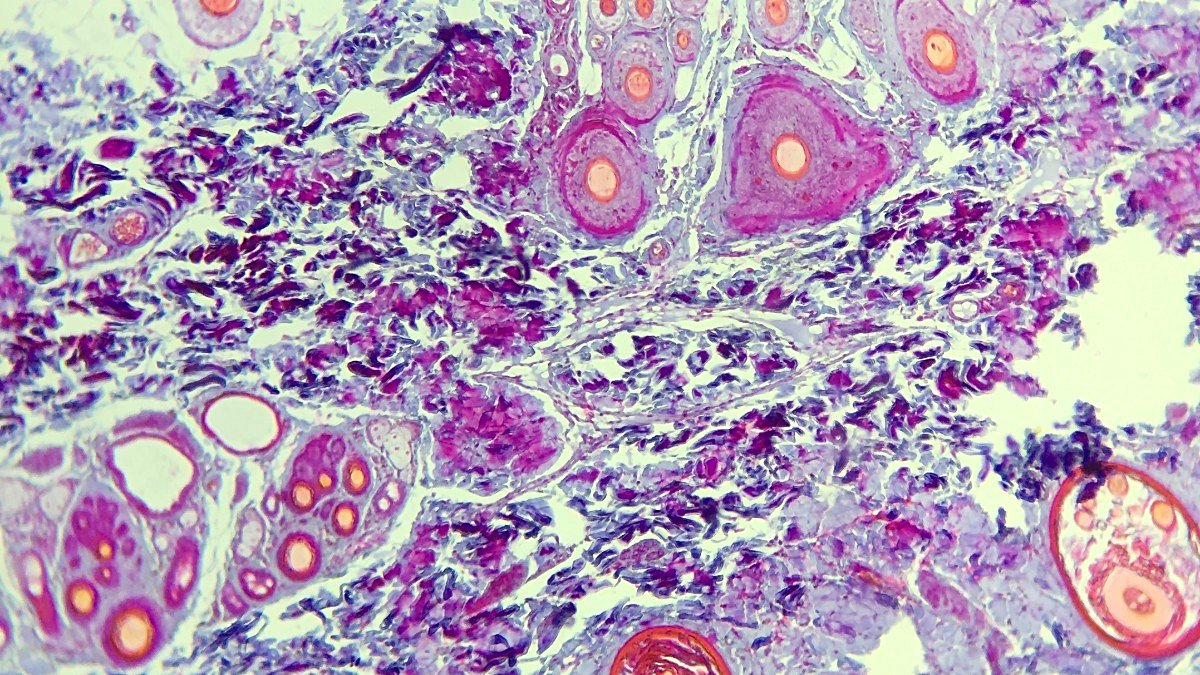

Lizozomlar ayrıca hücreye girebilecek hastalık yapıcı organizmaları yok etmek için hidroliz enzimlerini kullanırlar. Bağışıklık sisteminin bir parçası olan makrofaj hücreleri bu işlevi sık sık sergiler. Fagositoz adı verilen bu süreçte hücre zarının bir kısmı içeri doğru çökerek patojeni içine alır. Sonrasında bu çukurun uçları birleşerek bir vezikül oluşturur ve vezikül hücre zarından ayrılır. Bu veziküller sonrasında lizozomlarla birleşir ve lizozom içerisindeki hidroliz enzimleri veziküle hapsedilen patojeni sindirir.